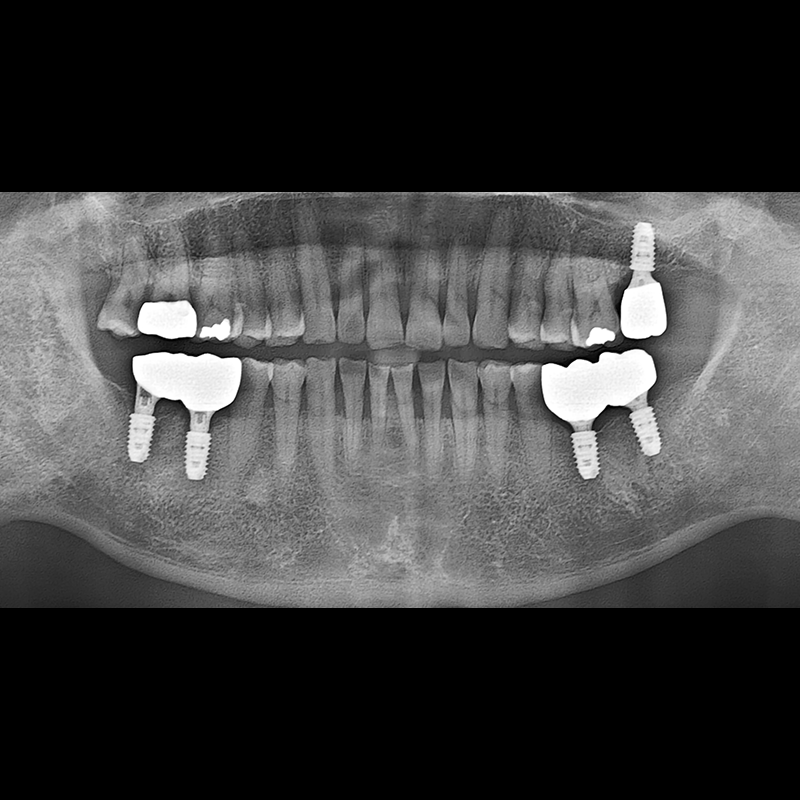

BEFORE AFTER

インプラント手術事例 2025.05.30

欠損した歯の部分と、生かしにくい歯の位置にインプラントを植立しました。